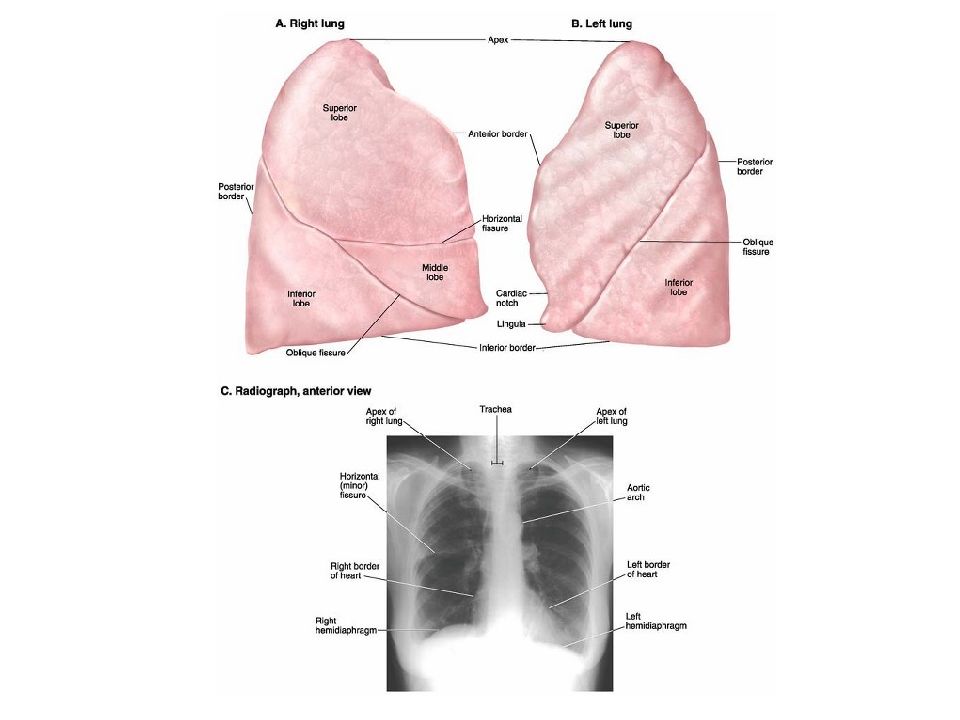

Анатомические изображения сегментов легких различных животных

Раздел: Другие животные